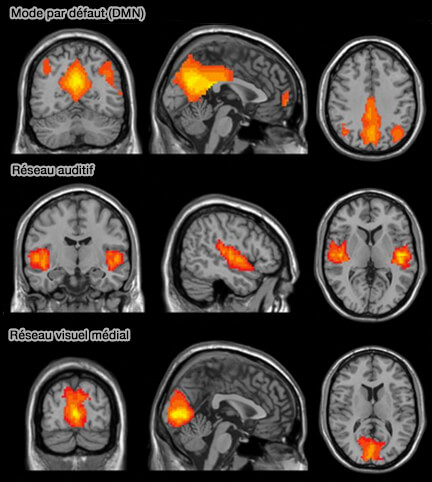

• IRMf de quelques réseaux

IRMf de quelques réseaux

(Figure : vetopsy.fr d'après Wang et coll)

Par contre, il faut faire attention à ne pas oublier le réseau du mode par défaut (DMN) du fonctionnement cérébral, i.e. quand le cerveau est au repos, mais actif et qu'il n'est pas accaparé par une tâche précise ou focalisé sur le monde extérieur (On the Stability of BOLD fMRI Correlations 2017).

Les données contemporaines du DMN suggèrent qu'il joue plutôt un rôle intégrateur dans la cognition, et ne présentent pas une vision aussi " négative " sur les tâches (loupepage spéciale sur le DMN).